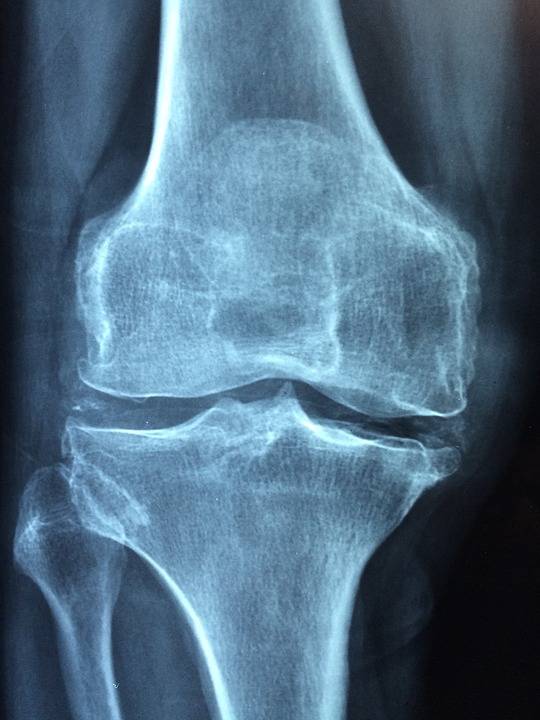

Entre autres, la cryothérapie corps entier est indiquée pour soulager les douleurs articulaires dus par exemple à de l'arthrose, à une polyarthrite rhumatoïde, à une spondylarthrite ankylosante, ou à diverses autres pathologies.

L'action de la cryothérapie corps entiers sur les douleurs articulaires est due aux réponses de l'organisme face au froid extrême et à leurs répercutions avec entre autres   :

- un effet analgésique

- un effet anti-inflammatoire

- un effet sur le flux sanguin, engendrant une meilleure oxygénation du sang et l'élimination des toxines (vasoconstriction et vasodilatation)